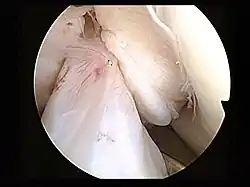

Arthroscopie diagnostique

La sécurité diagnostique la meilleure est obtenue par arthroscopie diagnostique. Ce procédé représente l'étalon-or pour le diagnostic de la rupture de LC. Ce procédé relève d'une chirurgie invasive au minimum, mais comporte certains risques, comme toute intervention chirurgicale dans le genou du patient[118]. Comme cependant le traitement chirurgical d'une rupture de LC sera conduit par chirurgie arthroscopique, il est possible d'enchaîner celle-ci immédiatement après l'arthroscopie diagnostique, par la résection partielle du ligament (pour une déchirure) ou la reconstruction en cas d'arrachement. Avec l'accroissement de la facilité de l'IRM, le nombre d'arthroscopies purement diagnostiques a nettement diminué ces dernières années[119],[120]. L'arthroscopie diagnostique est quand même utilisée comme précédemment comme procédé de choix pour une compréhension certaine du diagnostic de rupture de LC, en cas d'examen clinique confus et d'IRM difficile à interpréter[118].

Arthroscopie

L'opération proprement dite commence par l'introduction de l'arthroscope dans le genou du patient. Ceci permet de confirmer définitivement le diagnostic de rupture de LC. Les autres blessures, en particulier celles des ménisques, peuvent être soignées avant la reconstruction du LC.